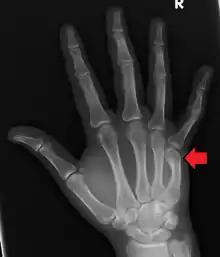

A boxer's fracture is the break of the 5th metacarpal bones of the hand near the knuckle.[4] Occasionally it is used to refer to fractures of the 4th metacarpal as well.[1] Symptoms include pain and a depressed knuckle.[2]

| Boxer's fracture of the 5th metacarpal head from punching a wall | |

Classically, it occurs after a person hits an object with a closed fist.[3] The knuckle is then bent towards the palm of the hand.[3] Diagnosis is generally suspected based on symptoms and confirmed with X-rays.[3]

Diagnosis by a doctor’s examination is the most common, often confirmed by x-rays. X-ray is used to display the fracture and the angulations of the fracture. A CT scan may be done in very rare cases to provide a more detailed picture.